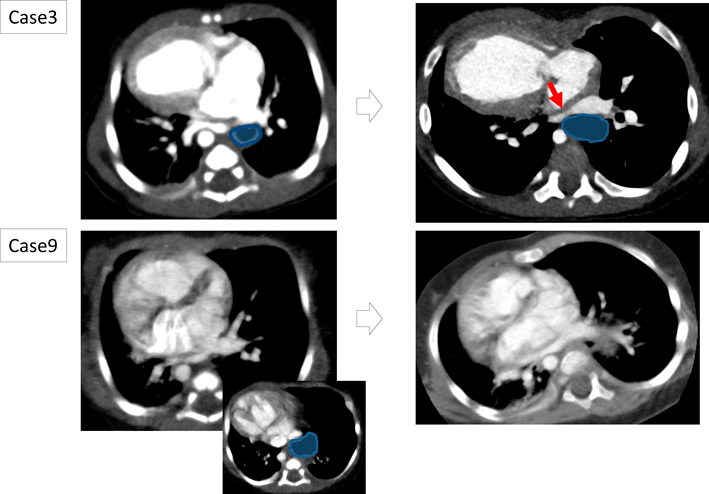

術後合併症として十二指腸狭窄合併が3例に認められた.症例5(Fig. 2)では,十二指腸狭窄解除術における術中所見で血管の走行異常があった.靭帯に覆われた肝動脈が十二指腸前面を走行しており(十二指腸前肝動脈),滑脱していた全胃を腹腔内に還納したことにより十二指腸が異常靭帯と十二指腸前肝動脈に圧排されて狭窄を来していた.また症例6では,滑脱した全胃を腹腔内に還納後,十二指腸前方に総胆管が走行することが判明した.開腹手術に移行し十二指腸バイパス術を追加することにより,総胆管による十二指腸狭窄を回避した.

Fig. 2 Post operative duodenal obstruction due to compression by abnormal ligaments and vessels (Case 5)

A: Preoperative schema of abdominal organs. B: Postoperative contrast study of upper gastrointestinal tract. The contrast medium is stuck in the stomach due to duodenal stenosis. C: Operation record of re-operation. Abnormal ligaments and vessels (arrow) obstruct the duodenum.

また,肺静脈圧排群のうち症例3, 4, 非圧排群のうち症例8, 9, 12では経時的な漏斗胸の増悪を認めた.肺静脈圧迫群である症例3, 4は漏斗胸の進行に伴い肺静脈圧排が持続していたが,非圧排群である症例8, 9, 12は漏斗胸の増悪にもかかわらず肺静脈圧排の出現はなかった.Fig. 5に肺静脈圧排群である症例3,非圧排群である症例9の経時的変化を示す.漏斗胸は滑脱した胃による肺静脈圧排の増幅要因として影響していた.